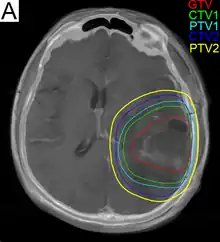

.png.webp)

Subsequent to surgery, radiotherapy becomes the mainstay of treatment for people with glioblastoma. It is typically performed along with giving temozolomide.[10] A pivotal clinical trial carried out in the early 1970s showed that among 303 GBM patients randomized to radiation or best medical therapy, those who received radiation had a median survival more than double those who did not.[69] Subsequent clinical research has attempted to build on the backbone of surgery followed by radiation. Whole-brain radiotherapy does not improve when compared to the more precise and targeted three-dimensional conformal radiotherapy.[70] A total radiation dose of 60–65 Gy has been found to be optimal for treatment.[71]